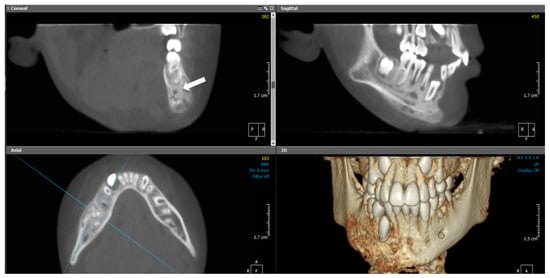

2.3. Case 3

2.3.1. History and Clinical Examination

2.3.2. Radiographic Examination

| 3 | 10 | Right mandible (#34–#47, crossing midline) | Granular sclerotic and radiolucent lesion, moth-eaten pattern, layered periosteal reaction | Normal viable bone, sterile | Empirical antibiotics, paracetamol, NSAIDs | CNO confirmed by imaging, CT, and sterile biopsy | NSAIDs only; no need for further escalation | Progressive improvement; under observation |